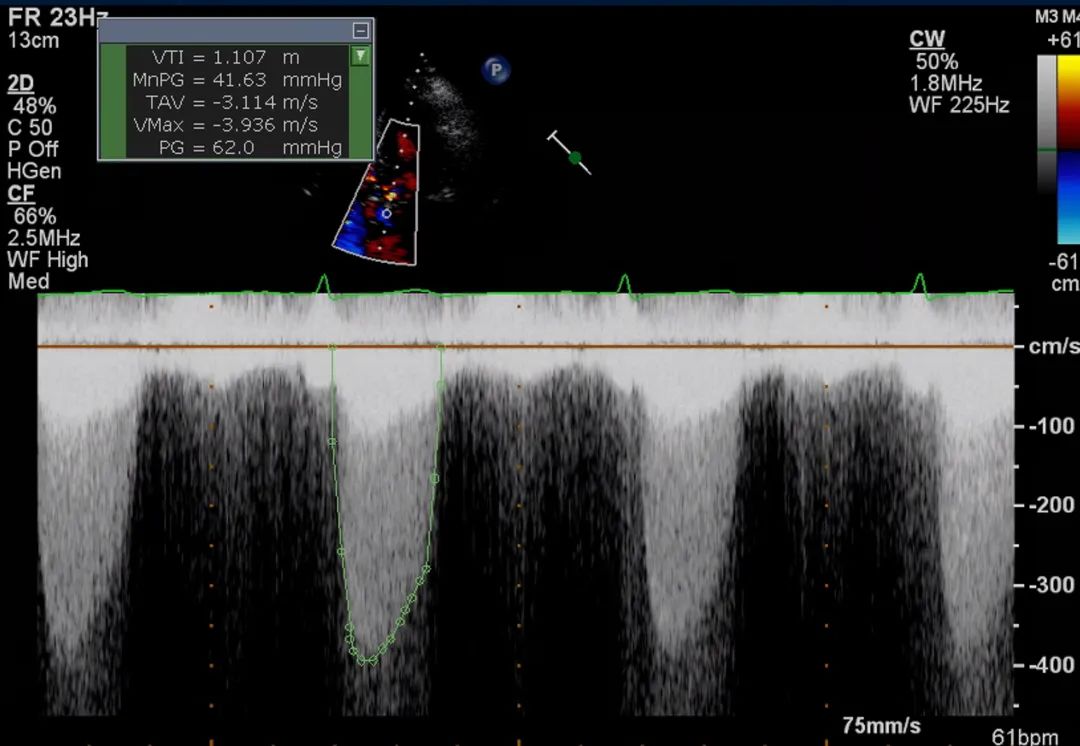

8、心尖五腔心切面:将连续多普勒(continuous-wave Doppler,CW)取样线对准主动脉瓣血流方向,测量主动脉瓣峰值流速和跨瓣压差,并评估是否存在主动脉瓣反流。测量主动脉瓣峰值流速波形(图9)。

图9. 心尖五腔心切面连续多普勒评估

心尖五腔心切面:将连续多普勒取样线对准主动脉瓣血流方向,测量主动脉瓣峰值流速(A)和跨瓣压差,并评估主动脉瓣反流(B)。